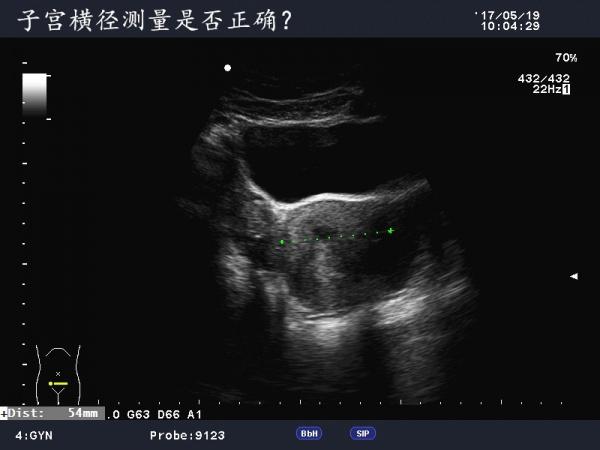

患者女,40Y,因下腹部疼痛就诊,最近一次月经来潮量少且疼痛厉害,以往基本上正常。

于月经第11天行B超检查。